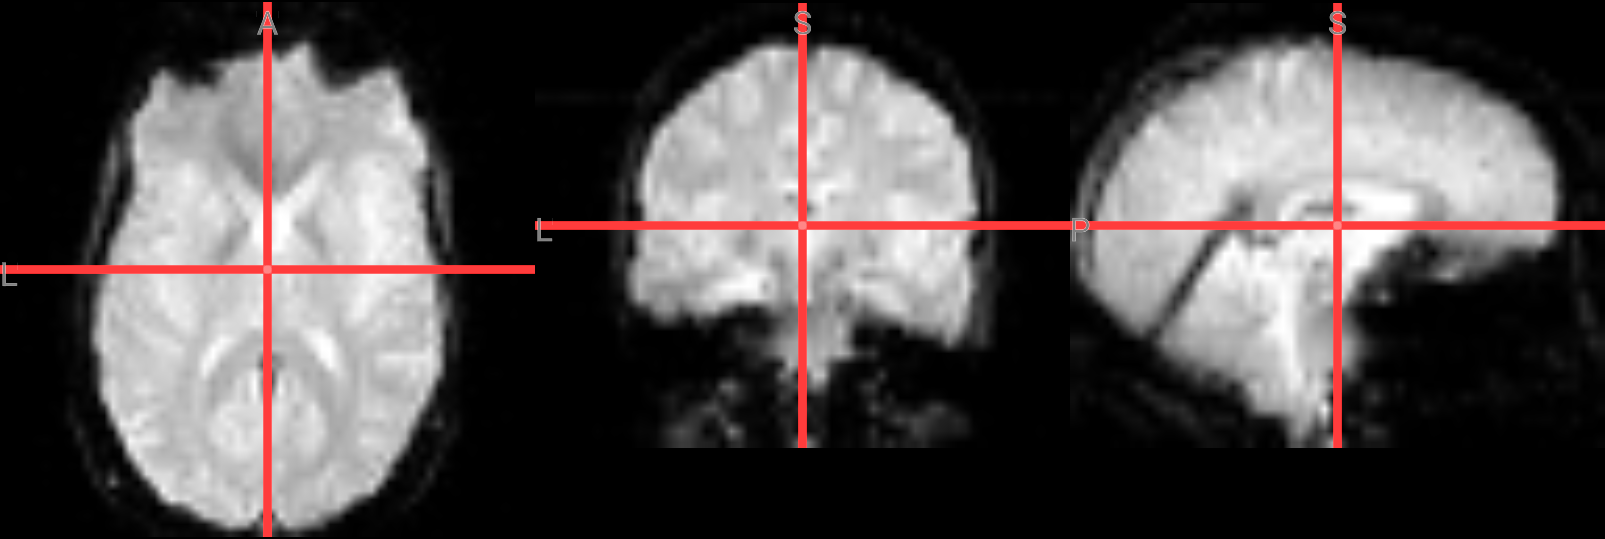

Checking Preprocessing#

Alignment

To visualize the alignment of functional run 1 in MNI space, the middle volume of the 4D dataset will be extracted and used as an overlay. Extracting a single volume instead of displaying the full 4D image reduces file size and computational load, making it more efficient for visualization and suitable for interactive display tools such as NiiVue.

index_img("./FSL_preproc/sub-08_task-flanker_run-2_bold_mcf_smooth_flirt2mni.nii.gz", middle_index1).to_filename("./FSL_preproc/sub-08_task-flanker_run-2_bold_mcf_smooth_flirt2mni_middle_3d.nii.gz")

# Verify the registration by overlaying the functional image on MNI

nv = NiiVue()

nv.load_volumes([

{"path": "/cvmfs/neurodesk.ardc.edu.au/containers/fsl_6.0.7.16_20250131/fsl_6.0.7.16_20250131.simg/opt/fsl-6.0.7.16/data/standard/MNI152_T1_2mm_brain.nii.gz", "colormap": "gray"},

{"path": "./FSL_preproc/sub-08_task-flanker_run-2_bold_mcf_smooth_flirt2mni_middle_3d.nii.gz", "colormap": "red", "opacity": 0.7}

])

nv

Image(url='https://raw.githubusercontent.com/NeuroDesk/example-notebooks/refs/heads/main/books/images/fsl_preproc_alignment.png')